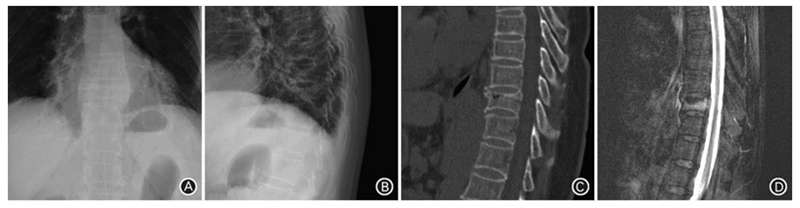

A、B. 术前正、侧位X线片示T10压缩骨折;C. 术前CT矢状位重建示T10压缩骨折;D. 术前MRI抑脂像示T10为新鲜骨折

患者女,73岁,摔伤致T10椎体压缩骨折,伤后3d行PCKP治疗。